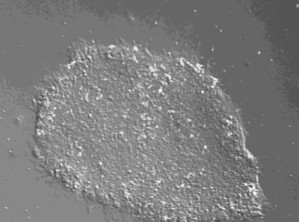

Human H1 ES 細胞(20継代)

未分化マーカーの発現を確認